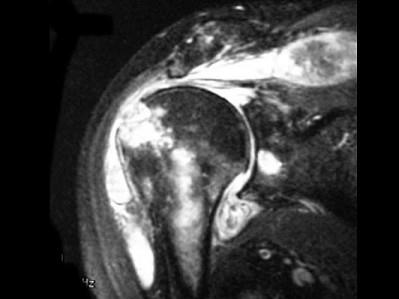

问题 女,71岁,左肩痛,系统性红斑狼疮服用高剂量的类固醇半年,结合图像,最可能的诊断是?(?)

选项 A.化脓性关节炎 B.类风湿关节炎 C.骨纤维肉瘤 D.肱骨头缺血坏死 E.肩关节结核

答案 E